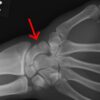

骨折や出血がある傷病者を手当てする場合は三角巾やガーゼ、

また身の回りにある物で固定などをしていきます。

その手順や搬送の仕方などを学びます。

普段、柔道整復師は包帯、ベッド、衛生用品その他全てがそろった状態で固定などしていきますが

現場では身の回りの物を工夫し使用する必要があります。

たとえば固定であれば雑誌、ダンボール、傘、木、野球のバッド、ボールペンなど…

咄嗟に対応することができればその人のケガも最小限に抑えることができます。